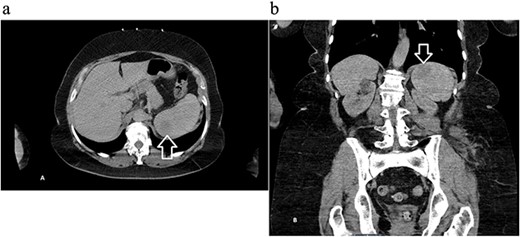

A 68-year-old female with a history of hypertension, gastroesophageal reflux disease, and hyperlipidemia was referred to the general surgery clinic for evaluation of a splenic mass found incidentally on a computed tomography (CT) scan performed in the emergency department, after a tree branch fell and injured her left flank. The patient was complaining from left flank pain at the time of presentation, and her physical exam showed a small nontender bruise on her left flank. Laboratory results were within normal range. CT of the abdomen and pelvis with intravenous (IV) contrast revealed an indeterminate round 3.5-cm hypoattenuating lesion in the spleen (Fig. 1).

Computed tomography of the abdomen and pelvis with contrast showing an indeterminate round 3.5 cm hypo-attenuating lesion in the spleen: (a) axial and (b) coronal views with arrow marking the mass.